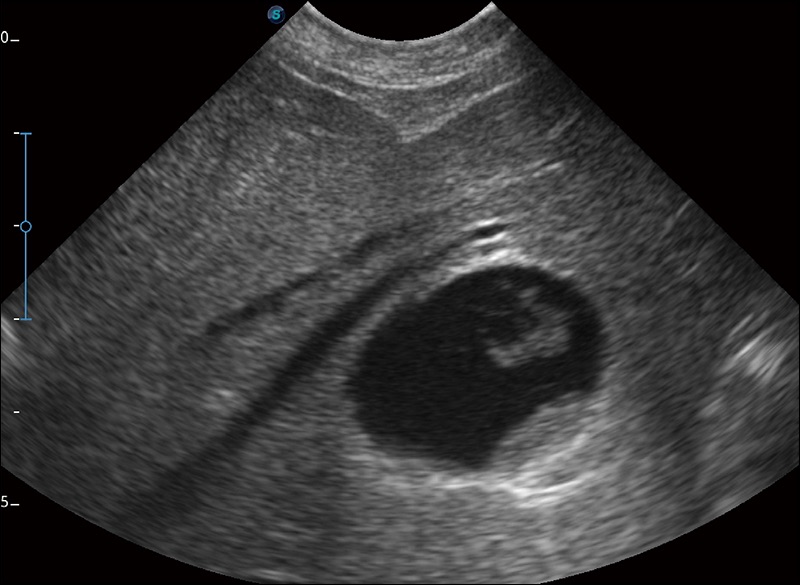

α1卓越的图像质量和便捷的工作流程,使每位宠物医生都能轻松扫查。其全面的兽用应用功能和紧凑型的结构设计,可以满足动物检查的多种需要。专业的预设检查模式和多领域测量软件包有助于为不同类型的动物提供检查, 让宠物医生能够出色的完成工作。

实时宽景成像

可实时观察感兴趣区域和病变位置